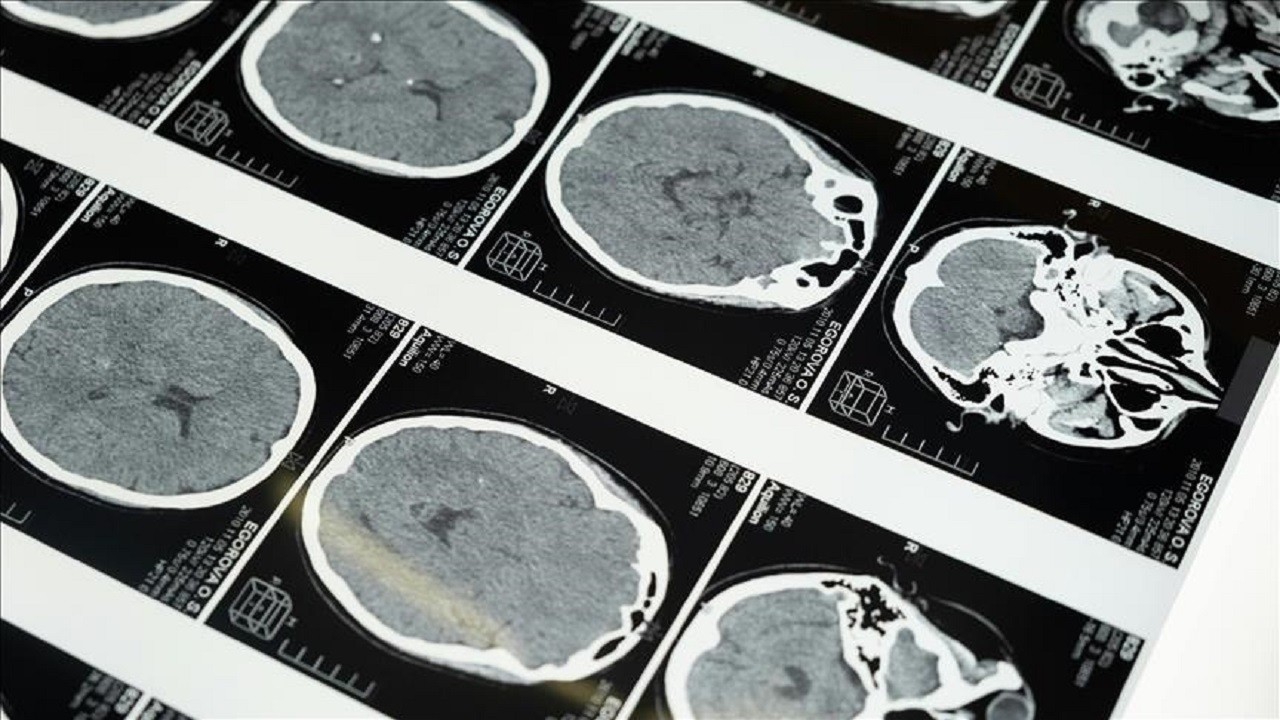

Aman dikkat! Prematüre bebekler için büyük risk

Uzmanlar prematüre bebeklerin göz sağlığı konusunda dikkatli olunması gerektiğini belirtiyor. Prematüre retinopatisi, erken teşhis ve hızlı tedavi edilmediğinde kalıcı görme kaybına yol açabiliyor.